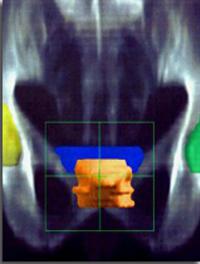

Le canal lombaire étroit est la première cause de chirurgie du rachis lombaire après 65 ans. La compression des structures neurologiques [...]

Le canal lombaire étroit est la première cause de chirurgie du rachis lombaire après 65 ans. La compression des structures neurologiques [...]